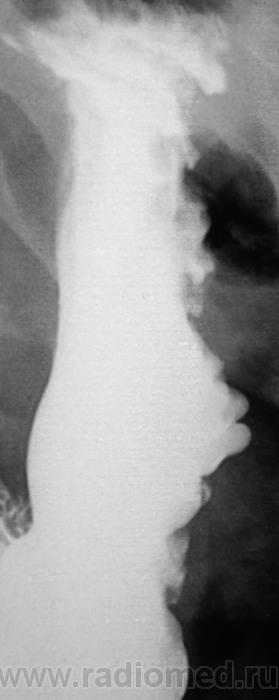

Варикозные вены?

Большая кривизна у тела желудка странная.

Да, для нормы странноватая.

Лежа бы вниз головой... Ну а так, дефект наполнения по большой кривизне свода. М.б. что угодно, больше за гиперплазию или онко.

Почему не локальная форма Менетрие?....

"Картинка" то типичная, именно, для болезни Менетрие.

Менетрие? По одному снимку, без второй порции бария, без шипучки и снимков в горизонтальном положении. Как-то лихо.